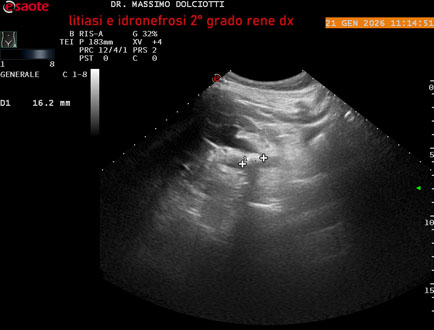

Data inserimento: 22/01/2026

Ecografia del: 21/01/2025

Strumento: Esaote MyLab Eight

Sonda: Convex Multifrequenza 1-8 MHz

Età Paziente: M 27 anni

Motivazione dell'esame: dolore al fianco destro da 3 mesi.

Commento all'esame: le immagini ed il video documentano il rene destro in sede, con ecostruttura disomogenea per evidenza, alla pelvi renale, di immagine iperecogena delle dimensioni di 16,2 mm, con cono d'ombra posteriore, da ricondurre a litiasi ed una formazione simile, di minore entità, al polo inferiore, delle dimensioni di 6,8 mm. Rene dx con diametro longitudinale di 122 mm (v.n. 90-120 mm) x 63 mm e parenchima renale dello spessore di 15 mm (v.n. > 13 mm). Rene dx con idronefrosi di 2° grado.

Conclusioni: litiasi e idronefrosi di 2° grado al rene destro (lithiasis and second-degree hydronephrosis of the right kidney).

In collaborazione: Dr.ssa Marica Manfredi - Ancona, Dr. Ilir Qose - Ancona

Presentazione: Dr. Massimo Dolciotti - Ancona

Elaborazione digitale: Andrea Dini - Ancona